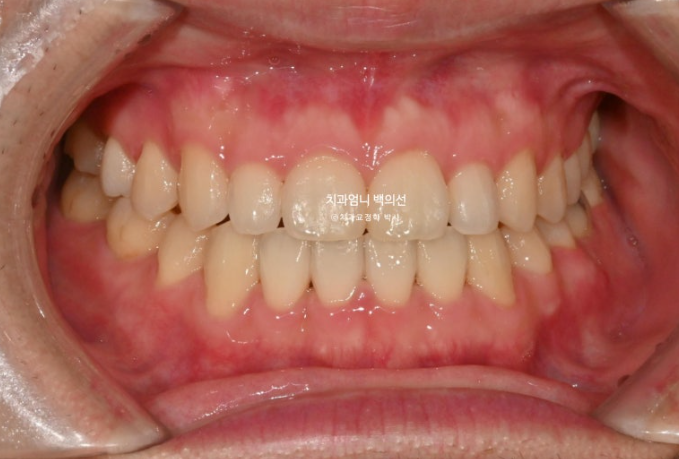

치료시작 1년 5개월 차 치료를 마무리 했습니다.

25.06

중심선은 잘 맞고 한쪽 어금니 반대교합은 별도의 악궁확장 없이 좋아졌습니다.

24.01~25.06

결손된 작은어금니 쪽으로 쓰러져 있던 큰어금니는 잘 세워졌습니다.

교합은 좋습니다.

아래 전체치열 후방이동으로 아래앞니가 뒤로 들어가며, 결과적으로 아랫입술이 뒤로 들어가며 입술 밸런스가 좋아졌습니다.

추가적인 발치나 양악수술 없이도 절충치료만으로 좋은 효과를 볼 수 있습니다